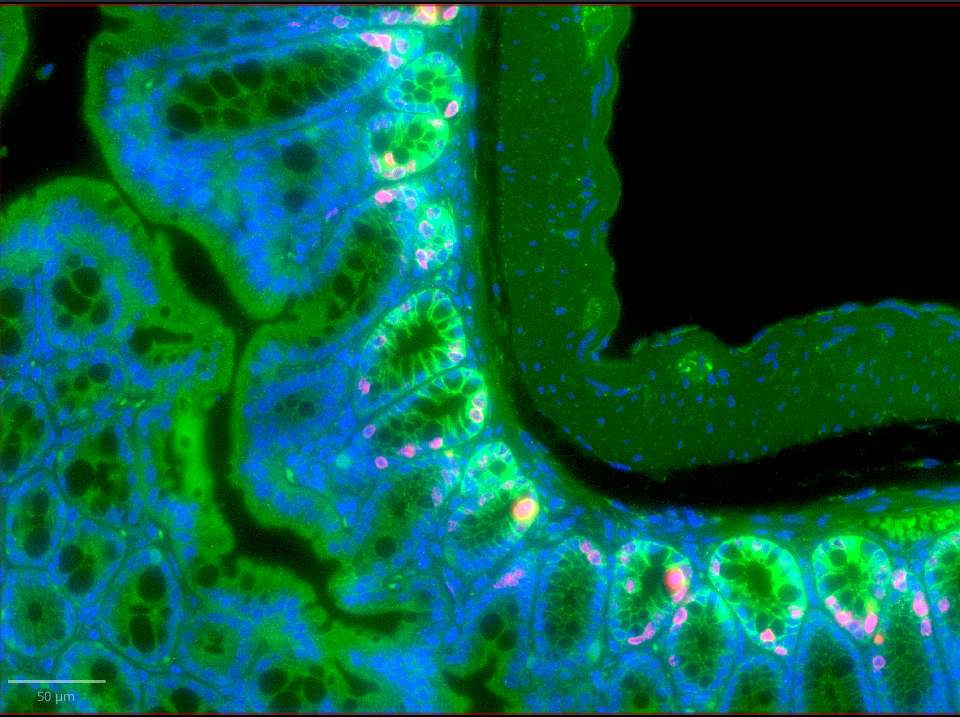

fluorescence image

Fig. 1.2 – A 3-channel image from fluorescence microscopy.